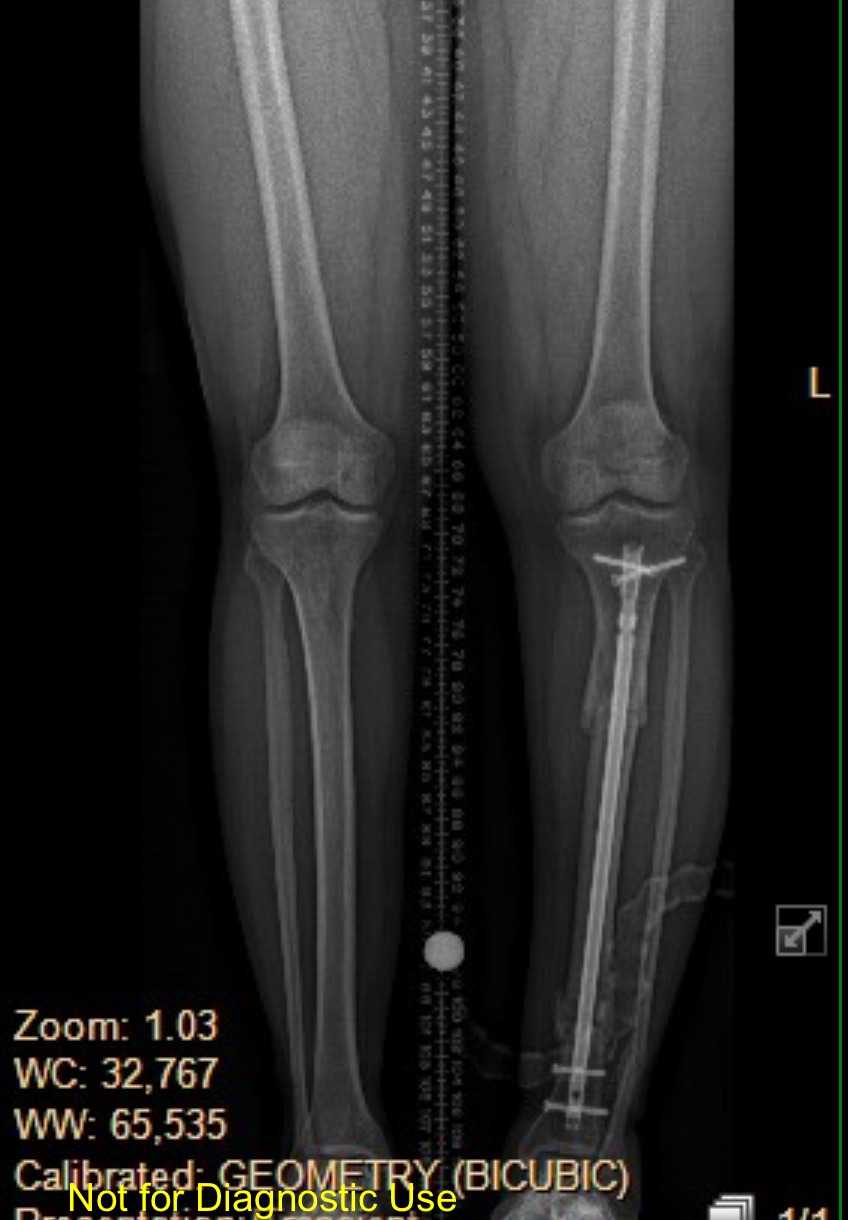

Last November I was struck by a motorcycle while crossing the street. My leg was broken in two places and I underwent surgery to put my leg back together. Until this point, I've been living on disability while I've been focused on my PT and child care for my niece.

After consulting with my doctor, we decided it would be best for me to have a corrective surgery. My left leg is now significantly deformed and if I don't have corrective surgery, I'll develop severe arthritis later in life. I have also not fully regained the mobility I had before the accident despite consistent PT. I'm still using a cane and it's difficult for me to walk or stand for extended periods of time.

My next surgery is scheduled for 9-22-25. I will need 4-6 months to recover.